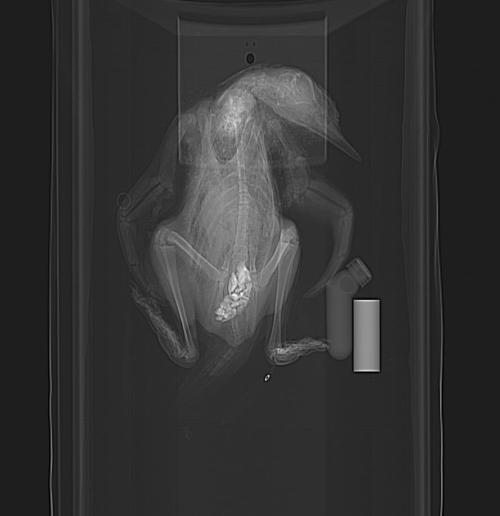

Young juvenile. Nice pose, and lots of anatomy is shown. And check it out- gastroliths?!? In such a young animal– is it even feeding yet? (presumably straight after hatching) And they are relatively big pebbles, too! If I noticed this 5 years ago, it would have been a nice paper to report- first recognition of gastroliths in penguin chicks seems to have been then. Indeed, that study observed some chicks intentionally swallowing stones.